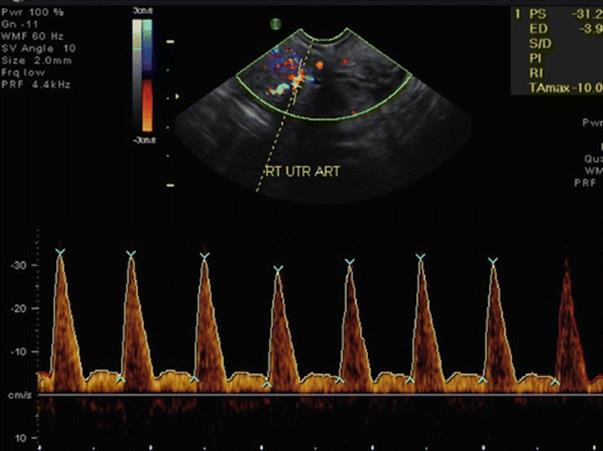

· Uterine Artery Blood Flow (Fig. 2.5)

Fig. 2.5

(a, b) Uterine artery and venous blood flow

· Lower uterine artery resistance index (RI) and higher PSV has a high incidence of OHSS.

· Uterine artery RI >0.79 is indicative of poor response and higher requirement of gonadotropin dose.

Luteal Phase Doppler

In the mid-luteal phase, the spiral artery RI is 0.48–0.52, uterine artery PI is 2.0–2.5, and uterine artery PSV is 15–20 (Fig. 2.16). Increased resistance to uterine blood flow in the mid-luteal phase is an important contributing factor in some cases of infertility. When pulsatility index (PI) is used as the measure of impedance, it was found that a PI of <3.0 [15] or <3.34 [16] was more favorable for pregnancy. No difference was found in uterine or ovarian artery PI between pregnant and non-pregnant women, but there was a non-significant increase in uterine receptivity when the uterine artery PI was in the range of 2.0–2.99 on the day of embryo transfer [17]. It was also seen that RI was found to be significantly lower at the time of oocyte collection in women who achieved a pregnancy [15]. In a recent study, Ng and colleagues [18] performed 3D ultrasound power Doppler 1 day after the LH surge in women undergoing frozen embryo transfer in natural or Clomiphene-induced cycles. These investigators found that endometrial thickness, endometrial volume, endometrial pattern, uterine PI, uterine RI, and endometrial and subendometrial 3D power Doppler flow indices were similar between the non-pregnant and pregnant groups [18]. They concluded that measurement of uterine artery blood flow should not be part of routine IVF practice. It was also emphasized in this study that the age of women was the only predictive factor for pregnancy. Early secretory transformation of endometrium is a feature of LPD [18].

Fig. 2.16

Luteal phase uterine artery blood flow